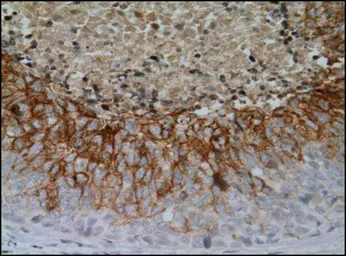

Anti-Carbonic Anhydrase IX antibody [GT12] used in IHC (Paraffin sections) (IHC-P). GTX70020

GTX70020 IHC-P Image

Immunohistochemical analysis of paraffin-embedded renal cell carcinoma (clear cell type) using anti-CAIX antibody [GT12] (GTX70020) at a dilution of 1:1000.